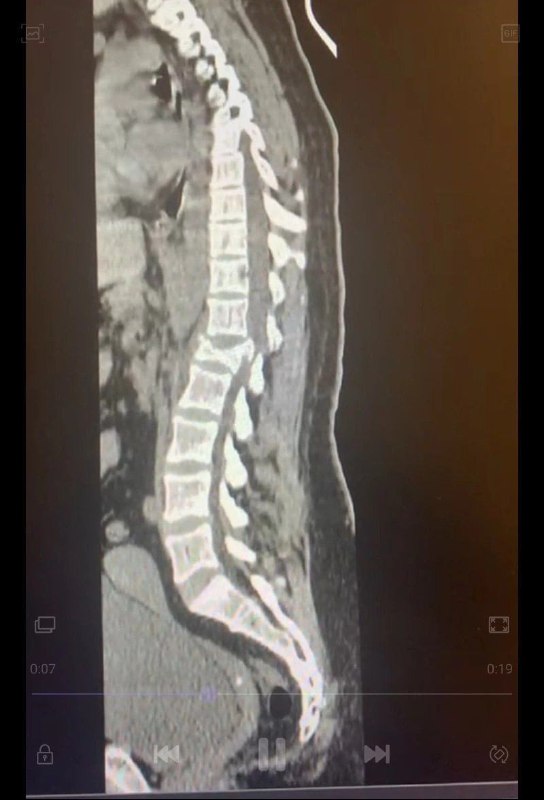

❄️ Будьте аккуратны с зимними забавамиКатание на плюшках под Красноярском обернулось для одной из девушек операцией на позвоночник. Теперь ей предстоят долгие месяцы реабилитации и восстановления.☝️ Между прочим, за эту зиму уже около 15 человек обратились в красноярскую травматологию с последствиями активного отдыха. Берегите себя! Перейти по ссылке